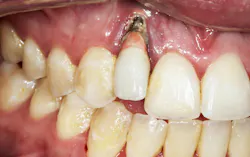

- Thinning of the hard and soft tissues around the dental implant (figure 2), which can increase the risk of a failed implant if tissue support is compromised

- Changes in occlusal patterns and force distribution, leading to possible fracturing of the implant components (figure 2a). Such changes can increase the risk of a failed implant and may require additional implant treatment to restore function and stability.

Gum recession around dental implants due to craniofacial development is a significant concern in implant dentistry, with the potential to undermine both the esthetic and functional success of dental implant procedures. When the gum tissue surrounding the implant site begins to recede, it can expose the underlying adjacent tooth root or the surface of the dental implant itself (figure 5). This not only affects the natural appearance of the artificial tooth but also increases the risk of dental implant failure and other complications.

Several risk factors other than jaw development contribute to gum recession around dental implants, including poor oral hygiene, gum disease (periodontal disease), teeth grinding, and even certain medical conditions. The esthetic impact of gum recession is particularly pronounced in the visible areas of the mouth, where the gumline plays a crucial role in the overall appearance of the smile. Receding gums can create an uneven gumline, expose the abutment screw or implant surface, and make the artificial tooth appear longer or mismatched compared to natural teeth. Additionally, exposed implant surfaces are more susceptible to bacterial accumulation, which can lead to peri-implantitis—a leading cause of dental implant complications and implant failure.

For patients who already exhibit signs of gum recession around their dental implants, advanced treatments such as bone grafting may be necessary to restore the supporting bone and stabilize the implant (figure 6). Addressing the underlying causes—such as correcting poor oral hygiene habits, managing teeth grinding, and treating existing gum disease—is critical to prevent recurrence and ensure the longevity of the implant.